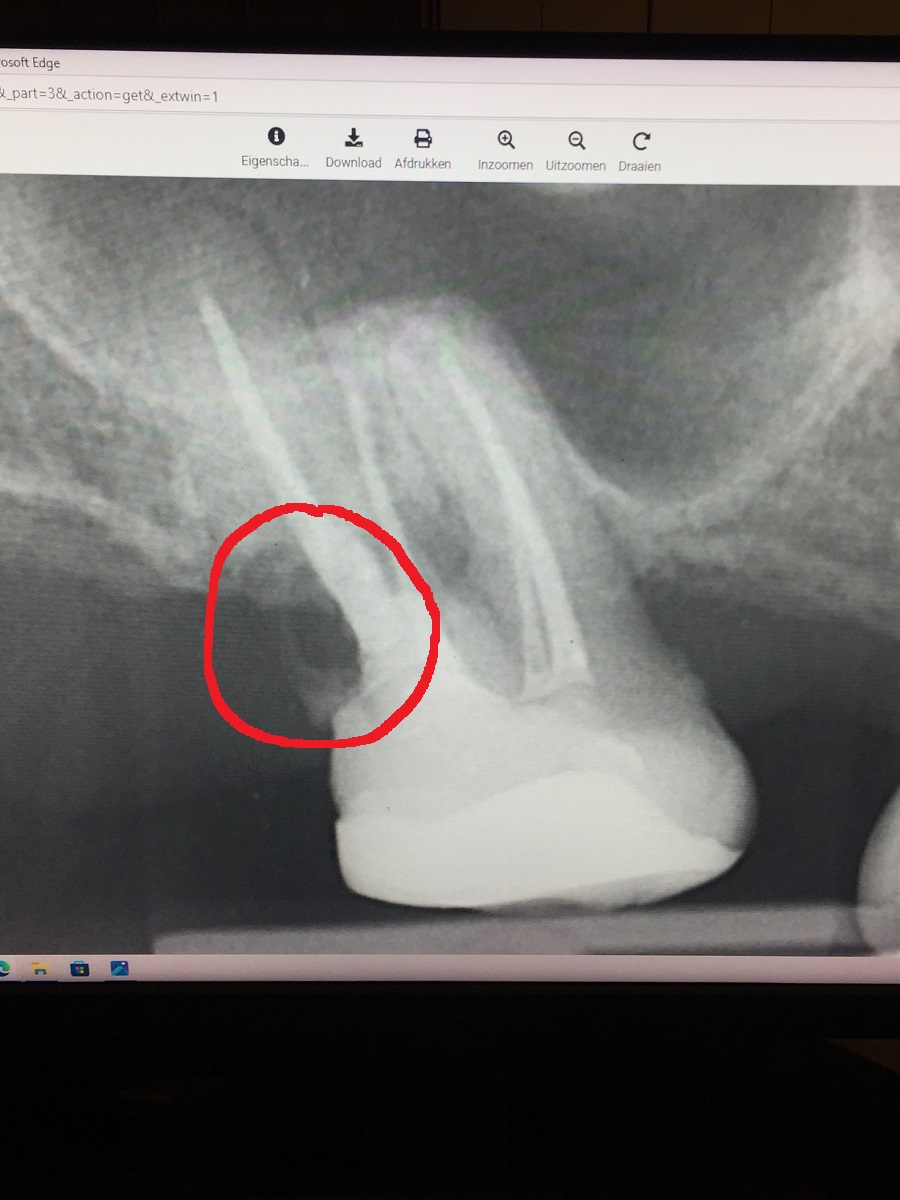

ik heb even een foto erbij voor Tandarts Richard .wat kunt u concluderen aan de hand van deze foto?

Attach

Tandarts_Richa…

idd lijkt op wortel resorptie. Element is helaas verloren. Oppassen voor mogelijke Antrum perforatie ( verbinding met neusholte) met verwijderen aangezien bot erg dun lijkt. Weet niet hoe de rest v h gebit eruit ziet.. maar nadenken over vervanging.

Ik heb dan ook nog een vraag over de kies 17 waar ik de foto van gepost heb. ik snap de foto zelf niet zo goed. kunt u mij eens uitleggen wat er precies te zien is? voor zover ik kan zien is er een flink stuk van de wortel weg waar het gebied zwart is en niet grijs. maar het wortelkanaal waar de vulling zit staat er nog gewoon. hoe kan dit gezien alles er rond heen weg is?

gezien hoe goed ik er nog op kan kauwen kan ik mij eigenlijk niet voorstellen dat het stuk van de wortel wat niet meer word weergegeven op de foto er niet meer zou zijn maar alles is mogelijk natuurlijk.

ik ben vroeger eens bij een inval tandarts geweest en die vertelde dat je een wortel kon laten polijsten .hij vermoedde toen dat er mogelijk een ontsteking kon zijn waar de perforatie zat en was gedicht met MTA. omdat hier bacteriën aan de buitenkant konden verblijven. het heeft ook zeker 2 weken geduurd voordat de endodontoloog de kies ging behandelen en het gat heeft gedicht nadat de wortel door de tandarts geperforeerd was.

eigenlijk had de tandarts dit gat al gelijk moeten dichten maar die had geen microscoop en wilde de kies niet meer aanraken. ik zie wel op de foto waar de wortel onderbroken is precies zit waar de kies in het verleden is geperforeerd. zie andere foto van direct na de endo 10 jaar geleden.